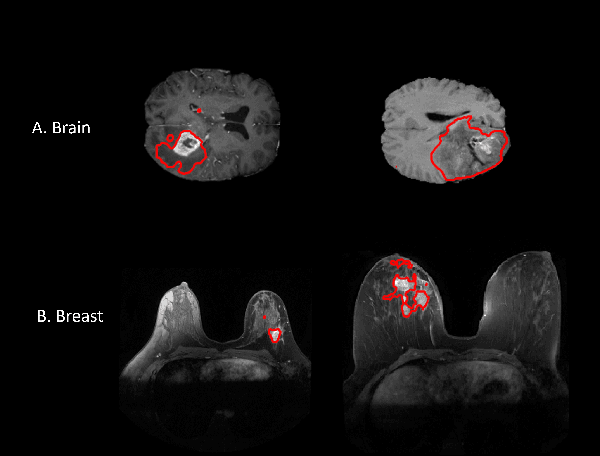

Abstract:Federated learning is increasingly being explored in the field of medical imaging to train deep learning models on large scale datasets distributed across different data centers while preserving privacy by avoiding the need to transfer sensitive patient information. In this manuscript, we explore federated learning in a multi-domain, multi-task setting wherein different participating nodes may contain datasets sourced from different domains and are trained to solve different tasks. We evaluated cross-domain federated learning for the tasks of object detection and segmentation across two different experimental settings: multi-modal and multi-organ. The result from our experiments on cross-domain federated learning framework were very encouraging with an overlap similarity of 0.79 for organ localization and 0.65 for lesion segmentation. Our results demonstrate the potential of federated learning in developing multi-domain, multi-task deep learning models without sharing data from different domains.